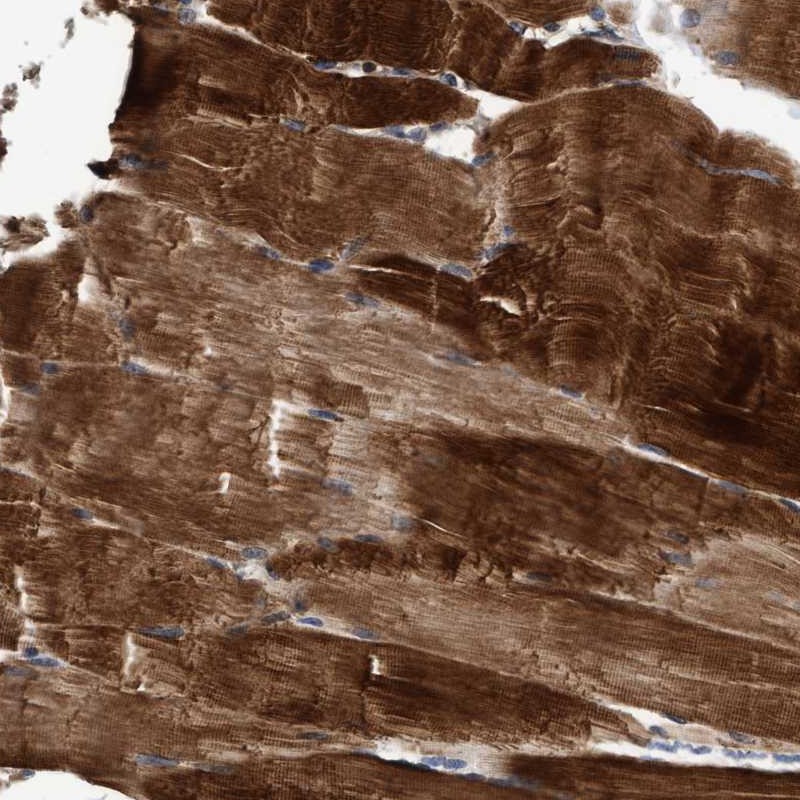

Immunohistochemical staining of human skeletal muscle shows strong cytoplasmic positivity in myocytes.